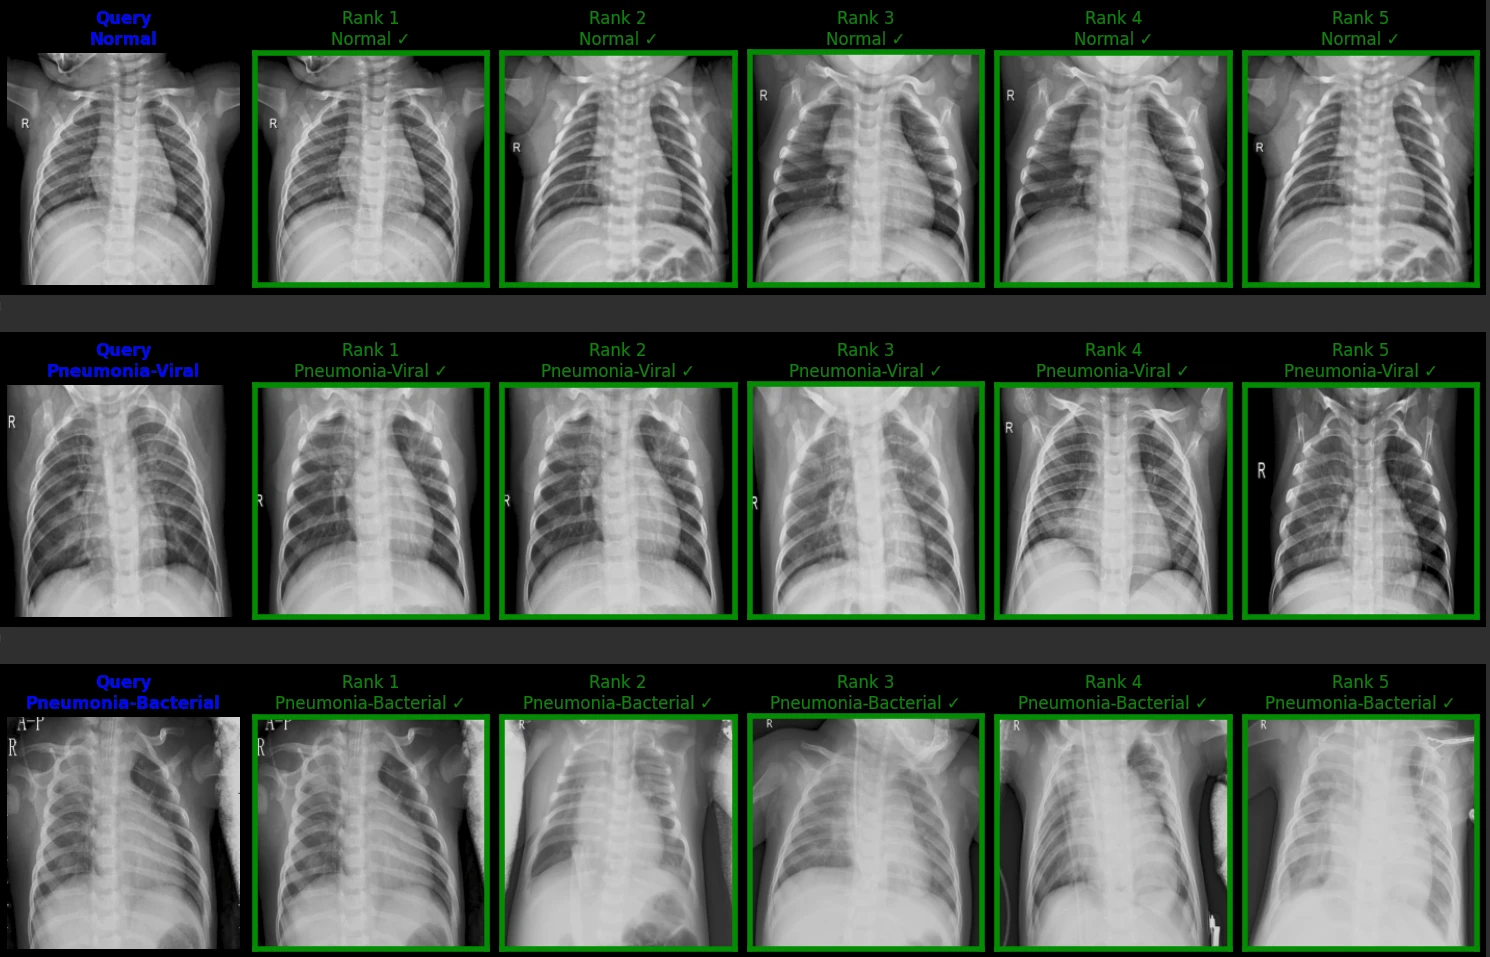

این پروژه با هدف ارتقای دقت و کارایی در سیستم‌های کمک‌تشخیصی (CAD)، یک موتور جستجوی محتوایی برای تصاویر X-Ray قفسه سینه را توسعه داده است. با عبور از محدودیت‌های مدل‌های CNN سنتی، در این طرح از معماری مدرن Vision Transformer برای استخراج ویژگی‌های بافت‌محور و تابع هزینه Quadruplet Loss برای بهینه‌سازی فضای برداری استفاده شده است. نتیجه نهایی، دستیابی به دقت SOTA (State-of-the-Art) با مدلی ۵ برابر سبک‌تر از راهکارهای پیشین است

Model: Swin Transformer (ViT)

Loss Function: Quadruplet Loss (Metric Learning)